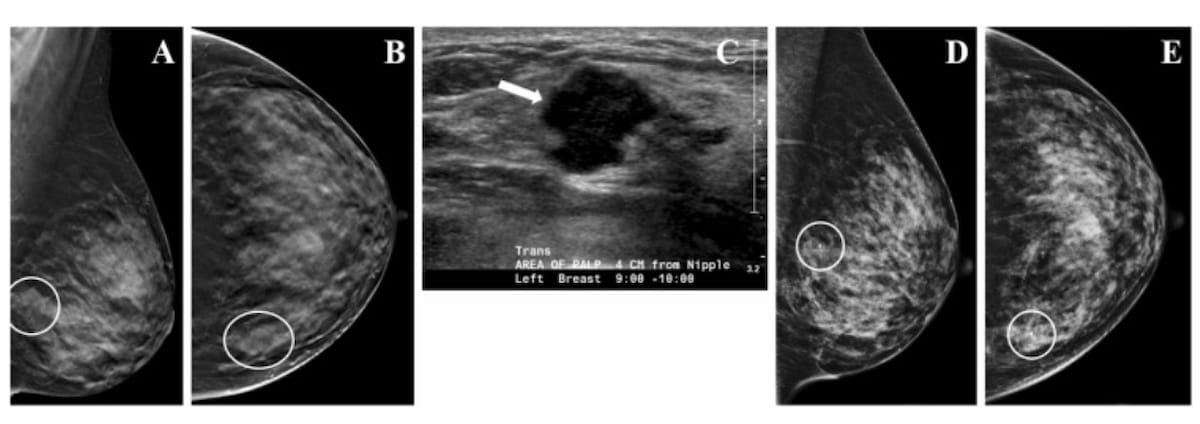

The combination of digital breast tomosynthesis (DBT) and molecular breast imaging (MBI) offered more than double the detection of invasive breast cancer with DBT in the first year of screening, according to a prospective study of nearly 3,000 women with dense breasts.

Digital breast tomosynthesis (DBT) and synthesized mammography offered a true-positive recall rate of 8.4 per 1,000 women screened vs. 6.2 for digital mammography alone, according to a study involving over 99,000 women.